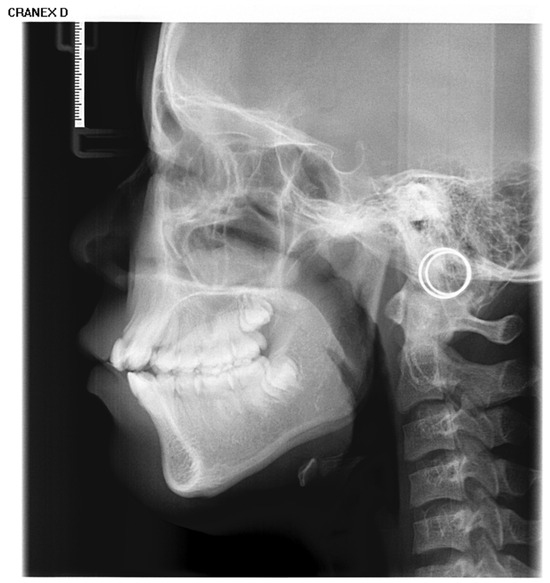

3.2. Visualization and Quantitative Analysis of Characteristics Related to Growth

Figure 6a,b presents the age-related average saliency maps for females aged 4 to 18 years, illustrating the distribution of developmental saliency across craniofacial regions in LCR images. To clearly demonstrate the anatomical correspondence of these salient regions, the saliency map of a representative 11-year-old subject is overlaid onto their original LCR image, showing the precise spatial alignment between salient areas and anatomical structures. For visualization, the saliency intensity is mapped to a color gradient from blue to red, where increasingly red hues indicate higher age-related saliency in the corresponding craniofacial region.

Figure 6.

Visualization of age-related saliency features. (a) Population-averaged age-related saliency maps for females aged 4–18 years; (b) Corresponding saliency maps for males. In (a,b), saliency is mapped on a blue-to-red gradient, with red indicating a higher Age-related Saliency Index (ASI). A representative saliency map from an 11-year-old subject is overlaid on the original LCR to illustrate anatomical correspondence. (c) Female ASI values across anatomical structures and ages. (d) Male ASI values across anatomical structures and ages.

The age-related saliency maps (Figure 6) revealed that during early development (ages 4–7 years), the sphenoid, temporal bones, and dentition exhibited high saliency (Figure 7a). At this stage, the outer background of the craniofacial contour in LCR images also showed relatively strong saliency. Quantitative analysis of the Age-related Saliency Index (ASI) for each anatomical structure (Figure 6 and Table 6 and Table 7) indicated that the saliency of both the temporal and sphenoid bones declined between ages 4 and 7. After age 8, the ASI for the maxilla and zygoma showed a synchronous, rapid increase (Figure 7b), whereas the ASI for the temporal bone remained at a low baseline without significant elevation. High saliency was observed in the mandible, as well as in internal anatomical regions such as the maxillary tuberosity and palatine process within the maxilla (Figure 7b,c), and the pterygoid process of the sphenoid bone.

Figure 7.

Anatomical structures exhibiting developmental saliency in average age-related saliency maps. (a) A 6-year-old female example (LCR with overlaid saliency map). Arrows indicate salient regions during the 4–7-year period: temporal bone, sphenoid region, orbit, and dentition. (b) A 12-year-old female example. Arrows highlight salient regions in the 8–12-year period: maxilla (tuberosity and palatine bone), zygomatic bone, pterygoid process, and cervical vertebrae. (c) An 18-year-old male example. Arrows point to salient regions in the 13–18-year period, including the maxilla, mandible, zygomatic bone, and cervical vertebrae.